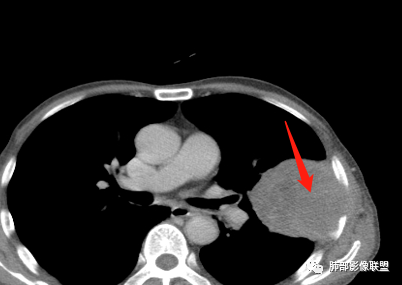

• 胸CT:左肺上叶实性占位,病灶与支气管无关,病灶对斜裂挤压,病灶周围光滑,未见分叶、毛刺;纵隔窗可见病灶内低密度区,病灶对胸壁侵袭,并可见肋骨破坏。

胸部CT所见左肺上叶尖后段胸膜下较大山丘形肿块,边界清楚,宽基底与胸膜相贴,边缘与胸膜呈直角及锐角相交。邻近上叶尖后段支气管受压推挤,叶裂局部膨隆,病灶周围见少许磨玻璃密度影,边界不清。纵膈窗显示,肿块密度均匀,增强扫描呈不均匀轻度强化,邻近肋骨骨质破坏,病变沿肋间隙向外侵犯,局部胸膜增厚。纵膈内见多发小淋巴结,未见胸腔积液征象。综合考虑恶性占位,肉瘤样癌可能性大。腰椎及髋部考虑骨转移。

鳞癌因为侵袭性力较强,容易直接侵犯胸膜、胸壁,而周围型肺癌侵犯胸壁的90%癌肿是鳞癌,这也是鳞癌的一个特征性表现。邻近胸壁的脂肪层消失,胸壁肿块形成或有肋骨皮髓质边界不清的侵蚀破坏(而非边缘硬化或崩解)是瘤体向周围直接侵犯的可靠征象。

鳞癌因为破坏力强,其内可见灶样坏死区,坏死边界不清,其内血管破坏彻底。